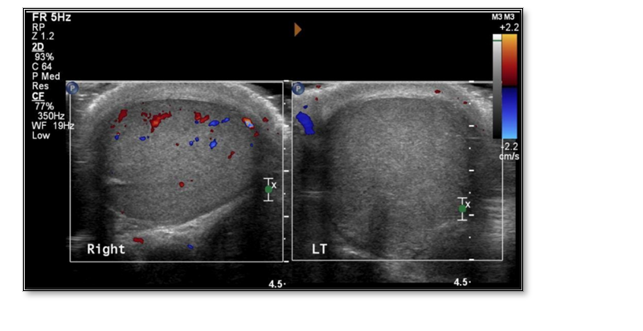

For blunt trauma, and in the hands of an experienced physician, bedside ultrasonography can be considered; vascular flow settings can be used to identify testicular rupture and compromised vascular flow (Figure 9).24 Clinicians should not rely on ultrasound for penetrating trauma; most penetrating scrotal injuries should be explored due to the limited sensitivity and variable levels of skill with ultrasound.15

Figure 9. Side-by-side Ultrasound with Doppler imaging. Note the decreased Doppler flow of the left testicle (LT) compared to the right. Original image by Dr. Allison Tadros (photo courtesy of WVU Department of Radiology).